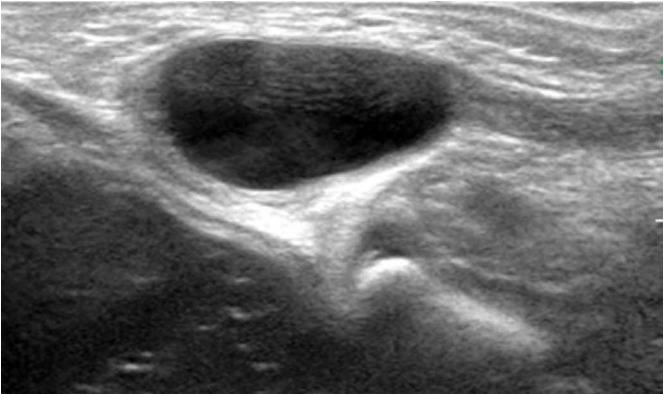

Groin lesions can be classified as neoplastic or non-neoplastic. Neoplastic lesions include lipoma, epidermoid cyst, angiomyofibroblastoma-like tumor, liposarcoma, and synovial sarcoma, as well as metastases from lymphoma, neuroendocrine carcinoma, and carcinomas of the lung, breast, urinary bladder, ovary, vulva, and colon. Non-neoplastic lesions include hernias, round ligament varices, endometriosis, Kimura disease, Castleman disease, hematoma, and inflammation. Because the clinical implications and therapeutic strategies for groin lesions vary depending on the cause, the ability to noninvasively differentiate among etiologies is very important. Although there is substantial overlap in ultrasonographic findings across various groin lesions, some ultrasonographic features, along with clinical characteristics, may suggest a specific diagnosis. Familiarity with the ultrasonographic and clinical features of various groin lesions facilitates accurate diagnosis and treatment.

腹股沟病变可分为肿瘤性或非肿瘤性。肿瘤性病变包括脂肪瘤、表皮样囊肿、血管肌纤维母细胞瘤样肿瘤、脂肪肉瘤和滑膜肉瘤,以及淋巴瘤、神经内分泌癌和肺癌、乳腺癌、膀胱癌、卵巢癌、外阴癌及结肠癌的转移瘤。非肿瘤性病变包括疝、圆韧带静脉曲张、子宫内膜异位症、木村病、卡斯特曼病、血肿和炎症。由于腹股沟病变的临床意义和治疗策略因病因不同而异,因此无创鉴别病因的能力非常重要。尽管各种腹股沟病变的超声表现有很大重叠,但一些超声特征结合临床特点可能提示特定诊断。熟悉各种腹股沟病变的超声和临床特征有助于准确诊断和治疗。